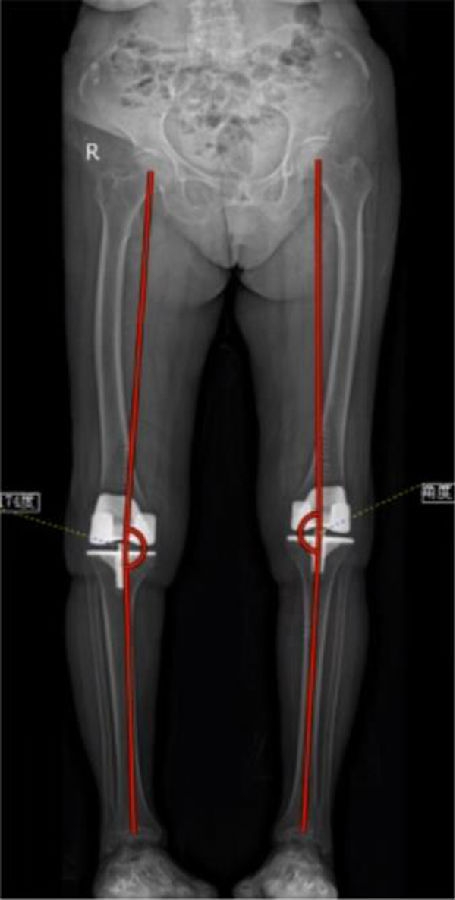

arKA组术后HKAA、cTCA明显小于aMA组,arKA组cFCA明显大于aMA组,差异均有统计学意义(p<0.05)。

由此,初步得出结论,导航辅助TKA应用arKA对线的可行性和有效性得到初步证实。该对线技术充分尊重周围软组织,为处理严重膝关节畸形提供了一种新的力线选择,在保护膝关节周围软组织和调控间隙平衡方面更具优势。

图16-17 术后